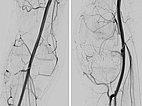

Digital subtraction angiography (DSA) of the knee (left AP projection, left lateral projection) shows an AVM with a rather spherical, aneurysmal nidus as well as another nidus intraosseously in the lateral tibial plateau. This very spherical, aneurysmal nidus together with the painful, progressive mass is suggestive of a PTEN hamartoma.